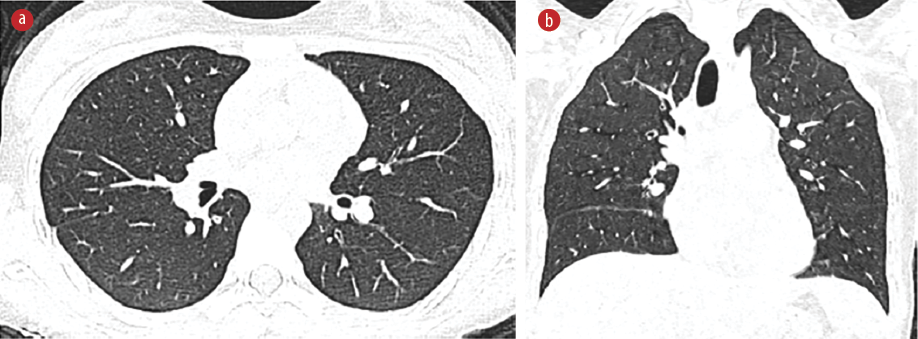

The patient underwent esophagogastroduod-enoscopy and colonoscopy. The esophagogastro-duodenoscopy was normal, but colonoscopy revealed moderate pancolitis involving the left side of the colon. Histological examination of a colonic biopsy was consistent with ulcerative colitis. Magnetic resonance enterography showed a mild circumferential mural thickening with hyperenhancement of the left colon. However, the visualized lung bases showed a few bilateral nodules. The chest computed tomography (CT) revealed multiple bilateral irregular pulmonary nodules with halo and feeding vessel signs [Figure 1]. Informed consent was obtained from the patient’s father.

Figure 1: High-resolution CT scan of lungs with (a) axial image showing multiple bilateral nodular opacities, most of which are peripheral and subpleural (red arrows). (b) Coronal image showing nodules with ill-defined borders with ground-glass halo (arrowhead).